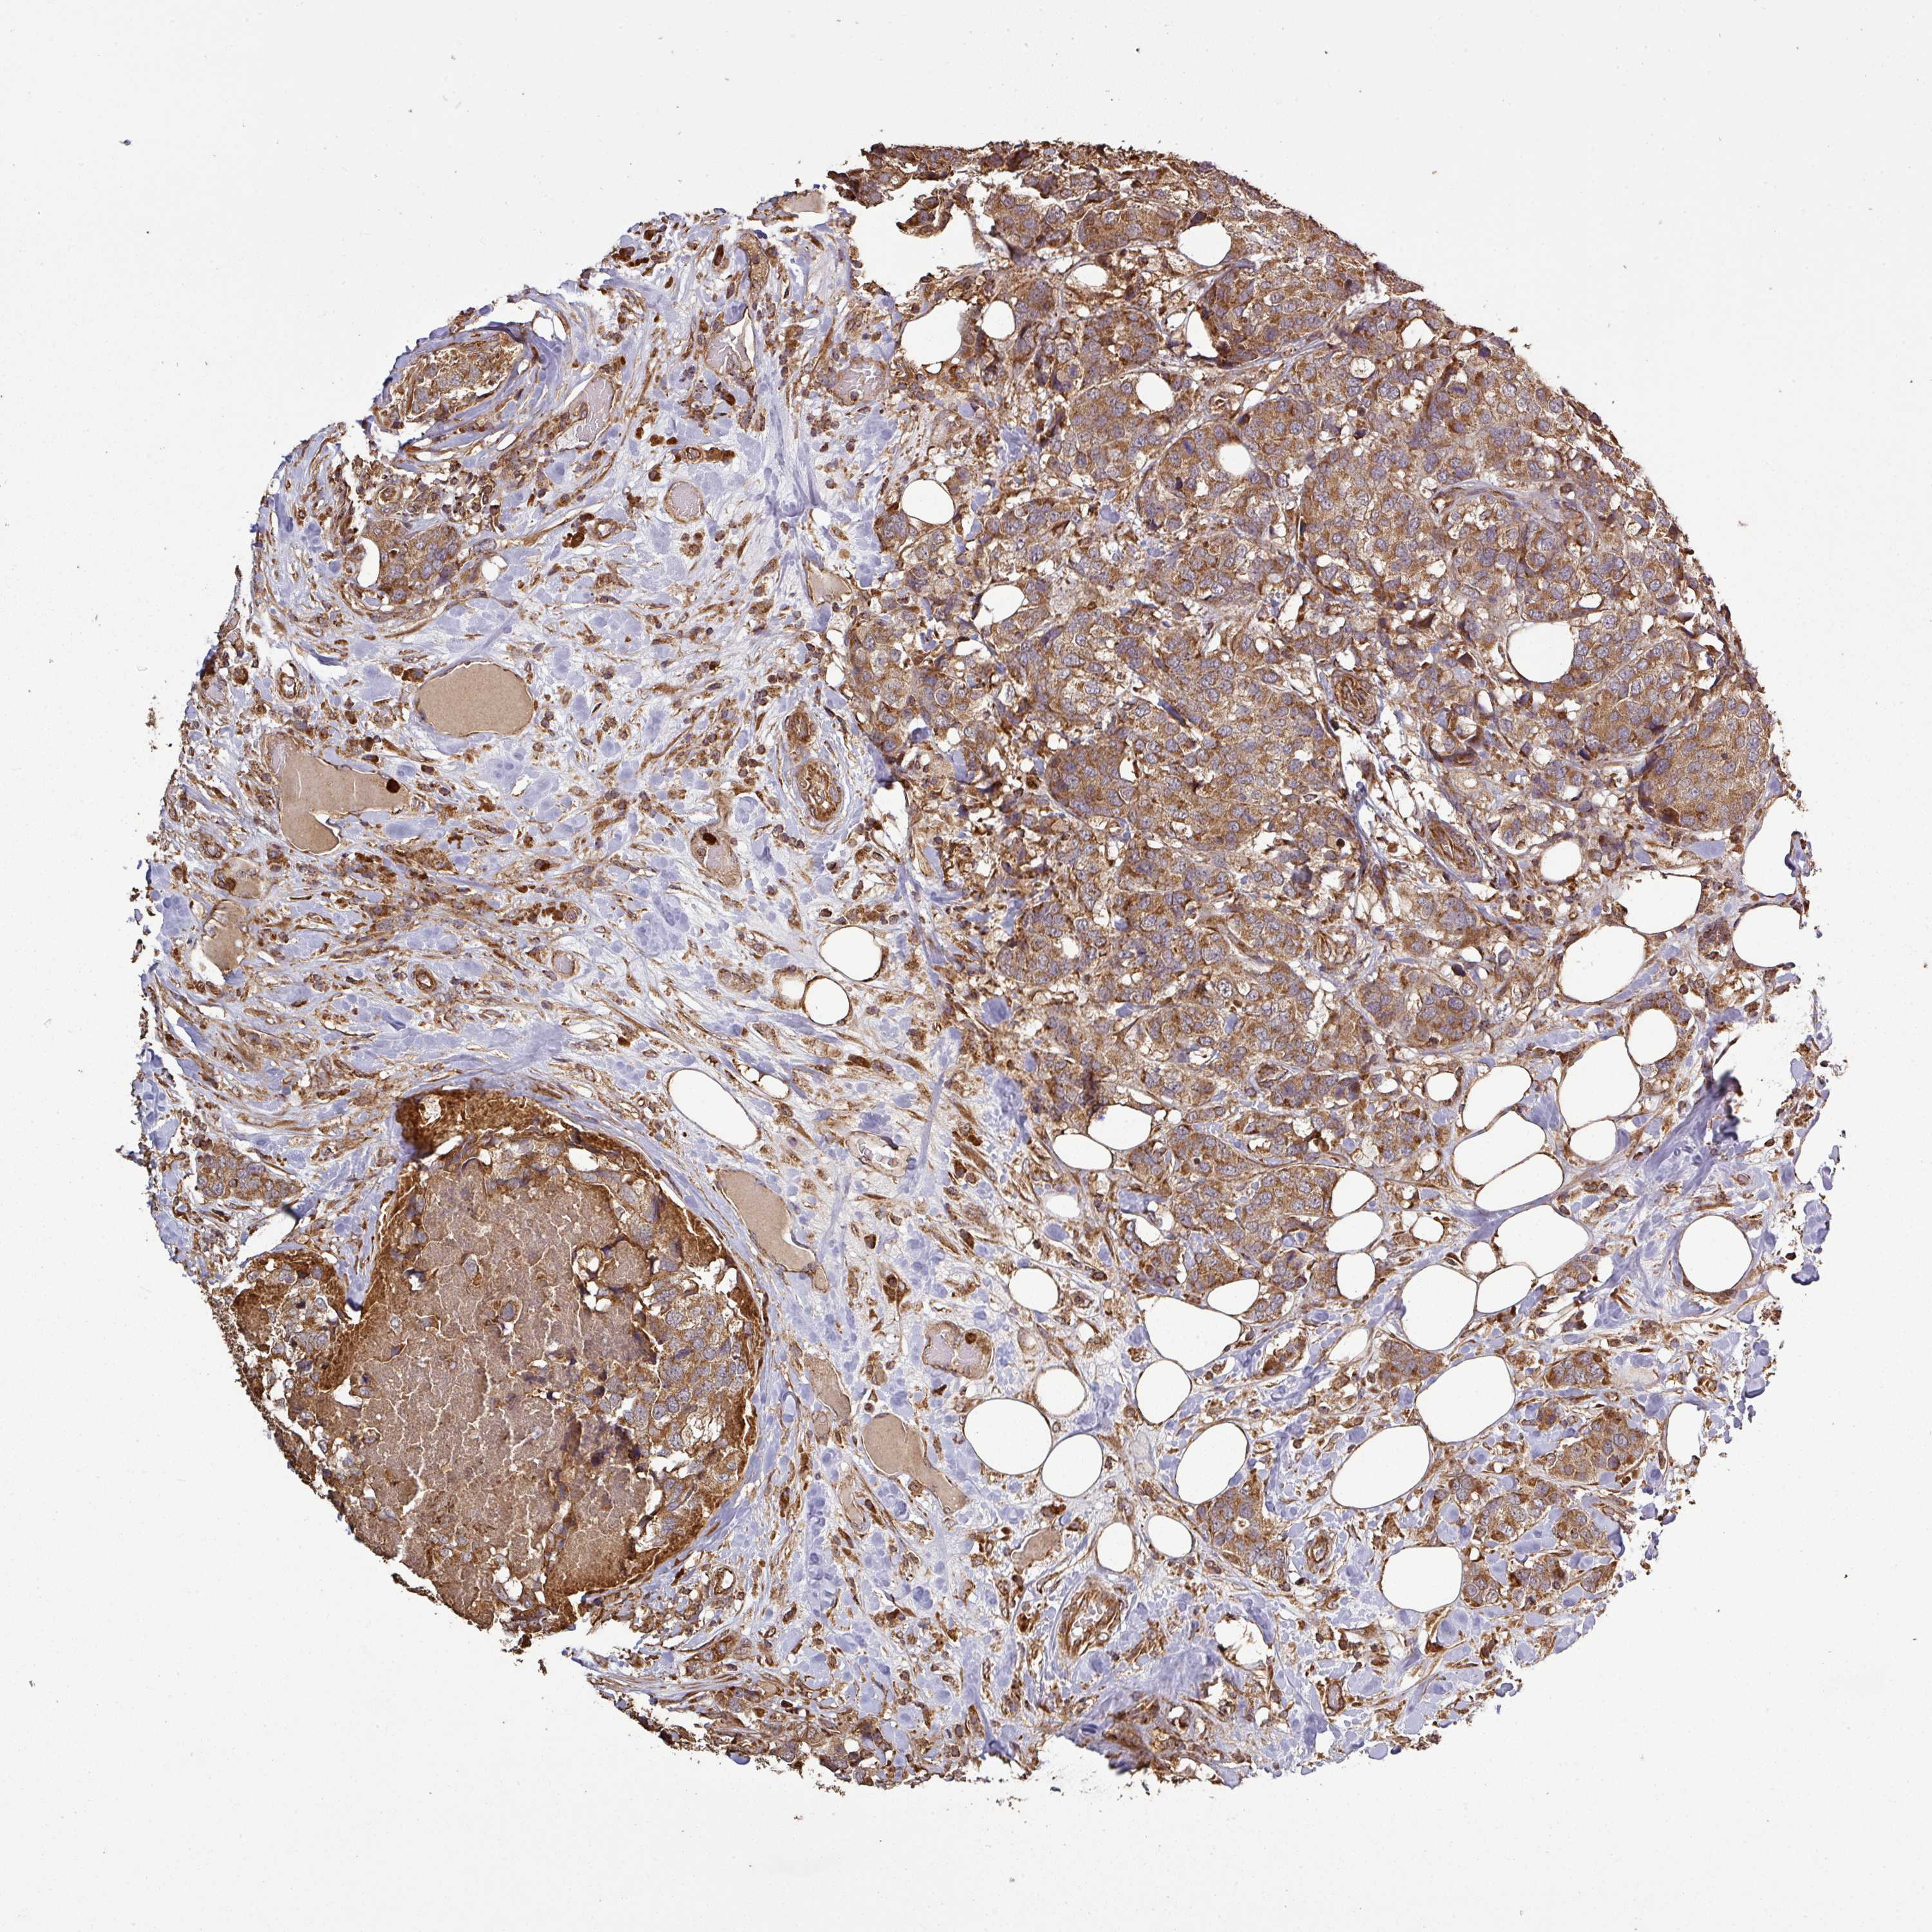

CANCER BREAST CANCER Show tissue menu

BRCA TCGA BRCA VALIDATION PROTEIN EXPRESSION

Breast cancer

Human cancer